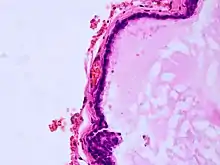

Histopathology of colloid cyst

A colloid cyst is a non-malignant tumor in the brain. It consists of a gelatinous material contained within a membrane of epithelial tissue. It is almost always found just posterior to the foramen of Monro in the anterior aspect of the third ventricle, originating from the roof of the ventricle. Because of its location, it can cause obstructive hydrocephalus and increased intracranial pressure. Colloid cysts represent 0.5–1.0% of intracranial tumors.[1]